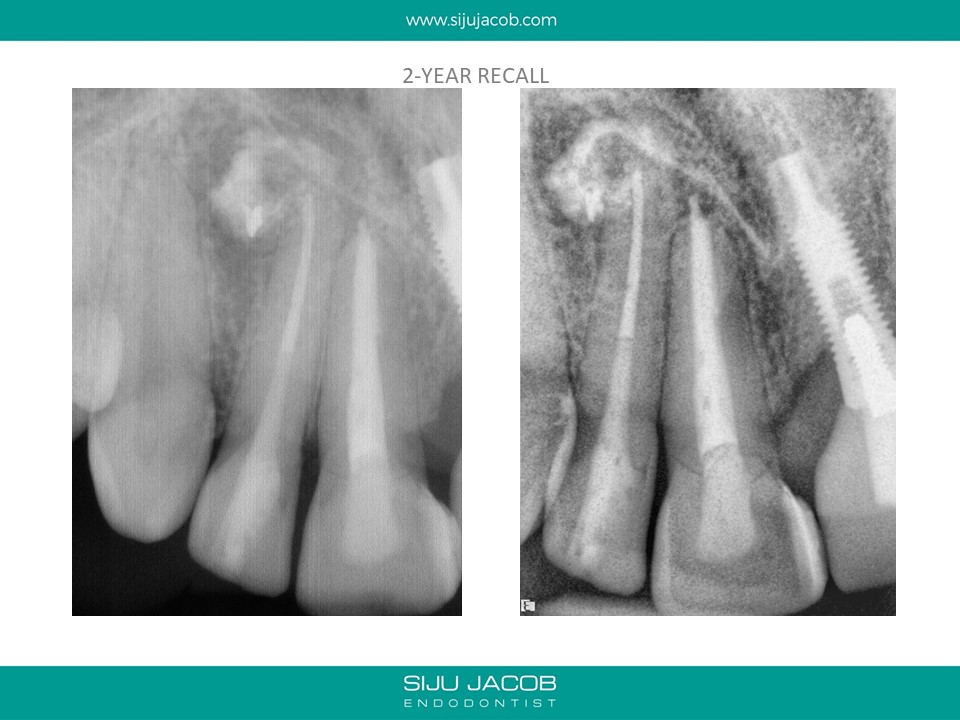

This patient was from The U.S. I re-treated a lateral incisor tooth of his while he was in Bangalore. He then went back to U.S. I received a mail from him two years later saying that the tooth we did was hurting. I thought that maybe, the lesion had recurred. I referred him to an Endodontist in the u.s who forwarded the radiograph to me. The lateral that I re-treated had healed well. It was an old central Incisor that had been treated much earlier that had fractured.